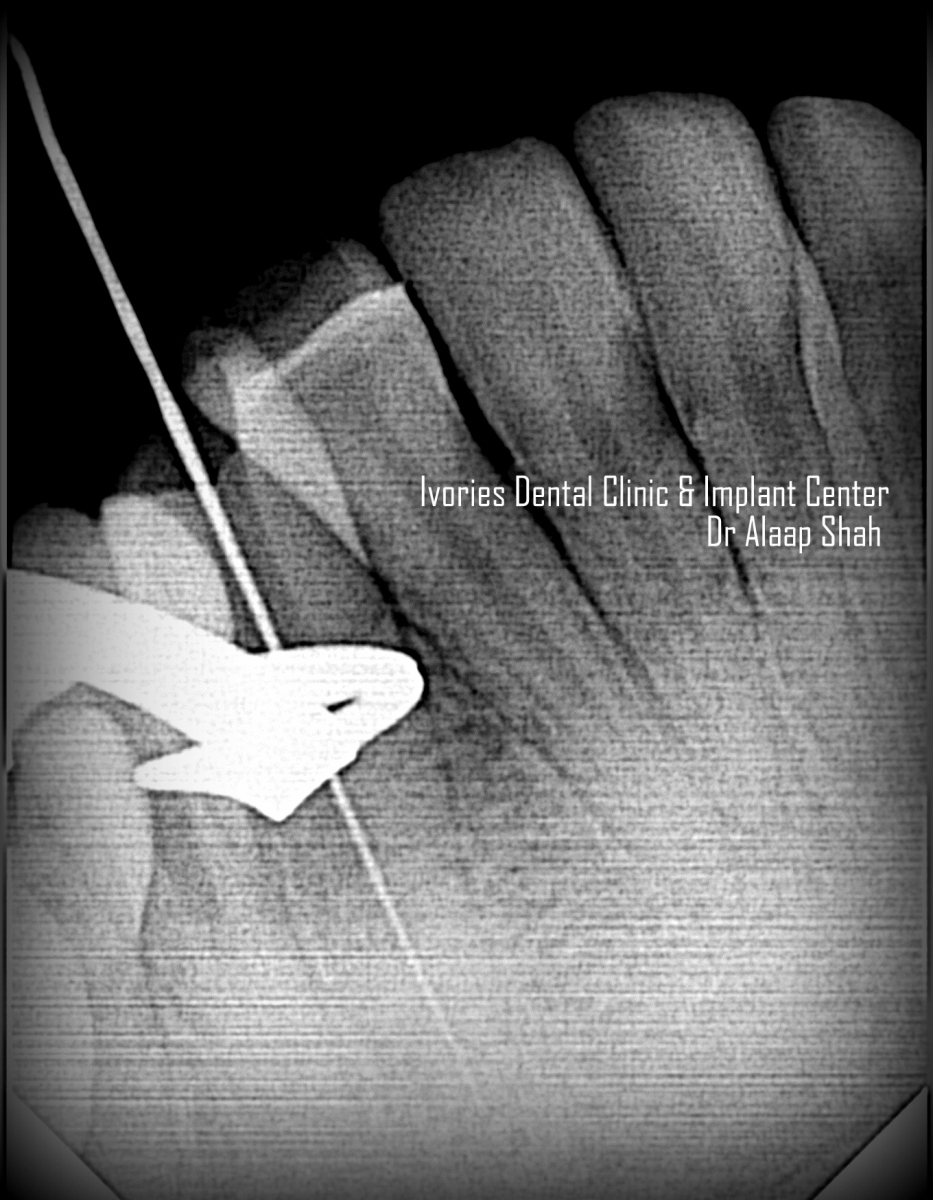

- Role & application of apex locators[J morrita, Propex2] Vs use of xrays

- WORKING LENGTH DETERMINATION WITH APEX LOCATORS